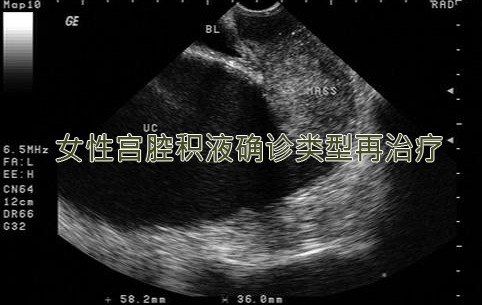

读宫腔积液知识 享孕育生命捷径

宫腔积液又称子宫积液,多伴发盆腔炎、附件炎及子宫内膜异位症等病症,在不孕症临床的治疗中属于疑难疾病,但临床发病率低于5%,不同年龄的子宫积液患者可由不同的原因所导致。出现子宫积液,患者可表现为下腹坠痛,同时可有白带增多以及血性分泌物,是导致女性不孕、流产的重要原因。

【分类】二类子宫积液要辩明

子宫积液,是子宫存在炎性渗出物,多数由于妇科的炎症引起。当发生炎症时内膜组织肿胀的细胞中会渗出略黏稠的液体,被四面组织包裹所慢慢形成的囊性包块。可分为生理性子宫积液和病理性子宫积液两类。